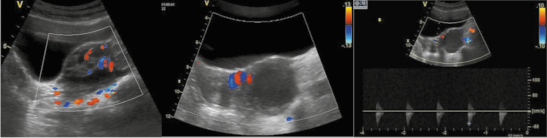

Все 24 (100%) ребенка, госпитализированные в стационар с подозрением на ППМ, характеризовались наличием косвенных признаков перекручивания по данным ректоабдоминального исследования и/или УЗИ, в том числе по результатам проведенного допплерометрического исследования сосудов и/или обнаружения симптома «пружинки» на амбулаторном этапе (рис. 1, 2), что вкупе с данными анамнеза и жалобами явилось причиной для ускоренного проведения оперативного лечения.

Рис. 1. Ультразвуковая картина при ППМ. Пациентка А., 6 лет: а – яичник увеличен в объеме, контуры четкие, неровные, эхогенность стромы неоднородно повышена, дифференцировка фолликулов снижена, определяются единичные по периферии; б – трансабдоминальное сканирование, поперечное сечение; левый яичник увеличен, расположен срединно, позади мочевого пузыря; дифференцировка снижена за счет отека стромы; в – при цветовом допплеровском картировании кровоток резко обеднен, определяется единичный артериальный сосуд в проекции ворот яичника.